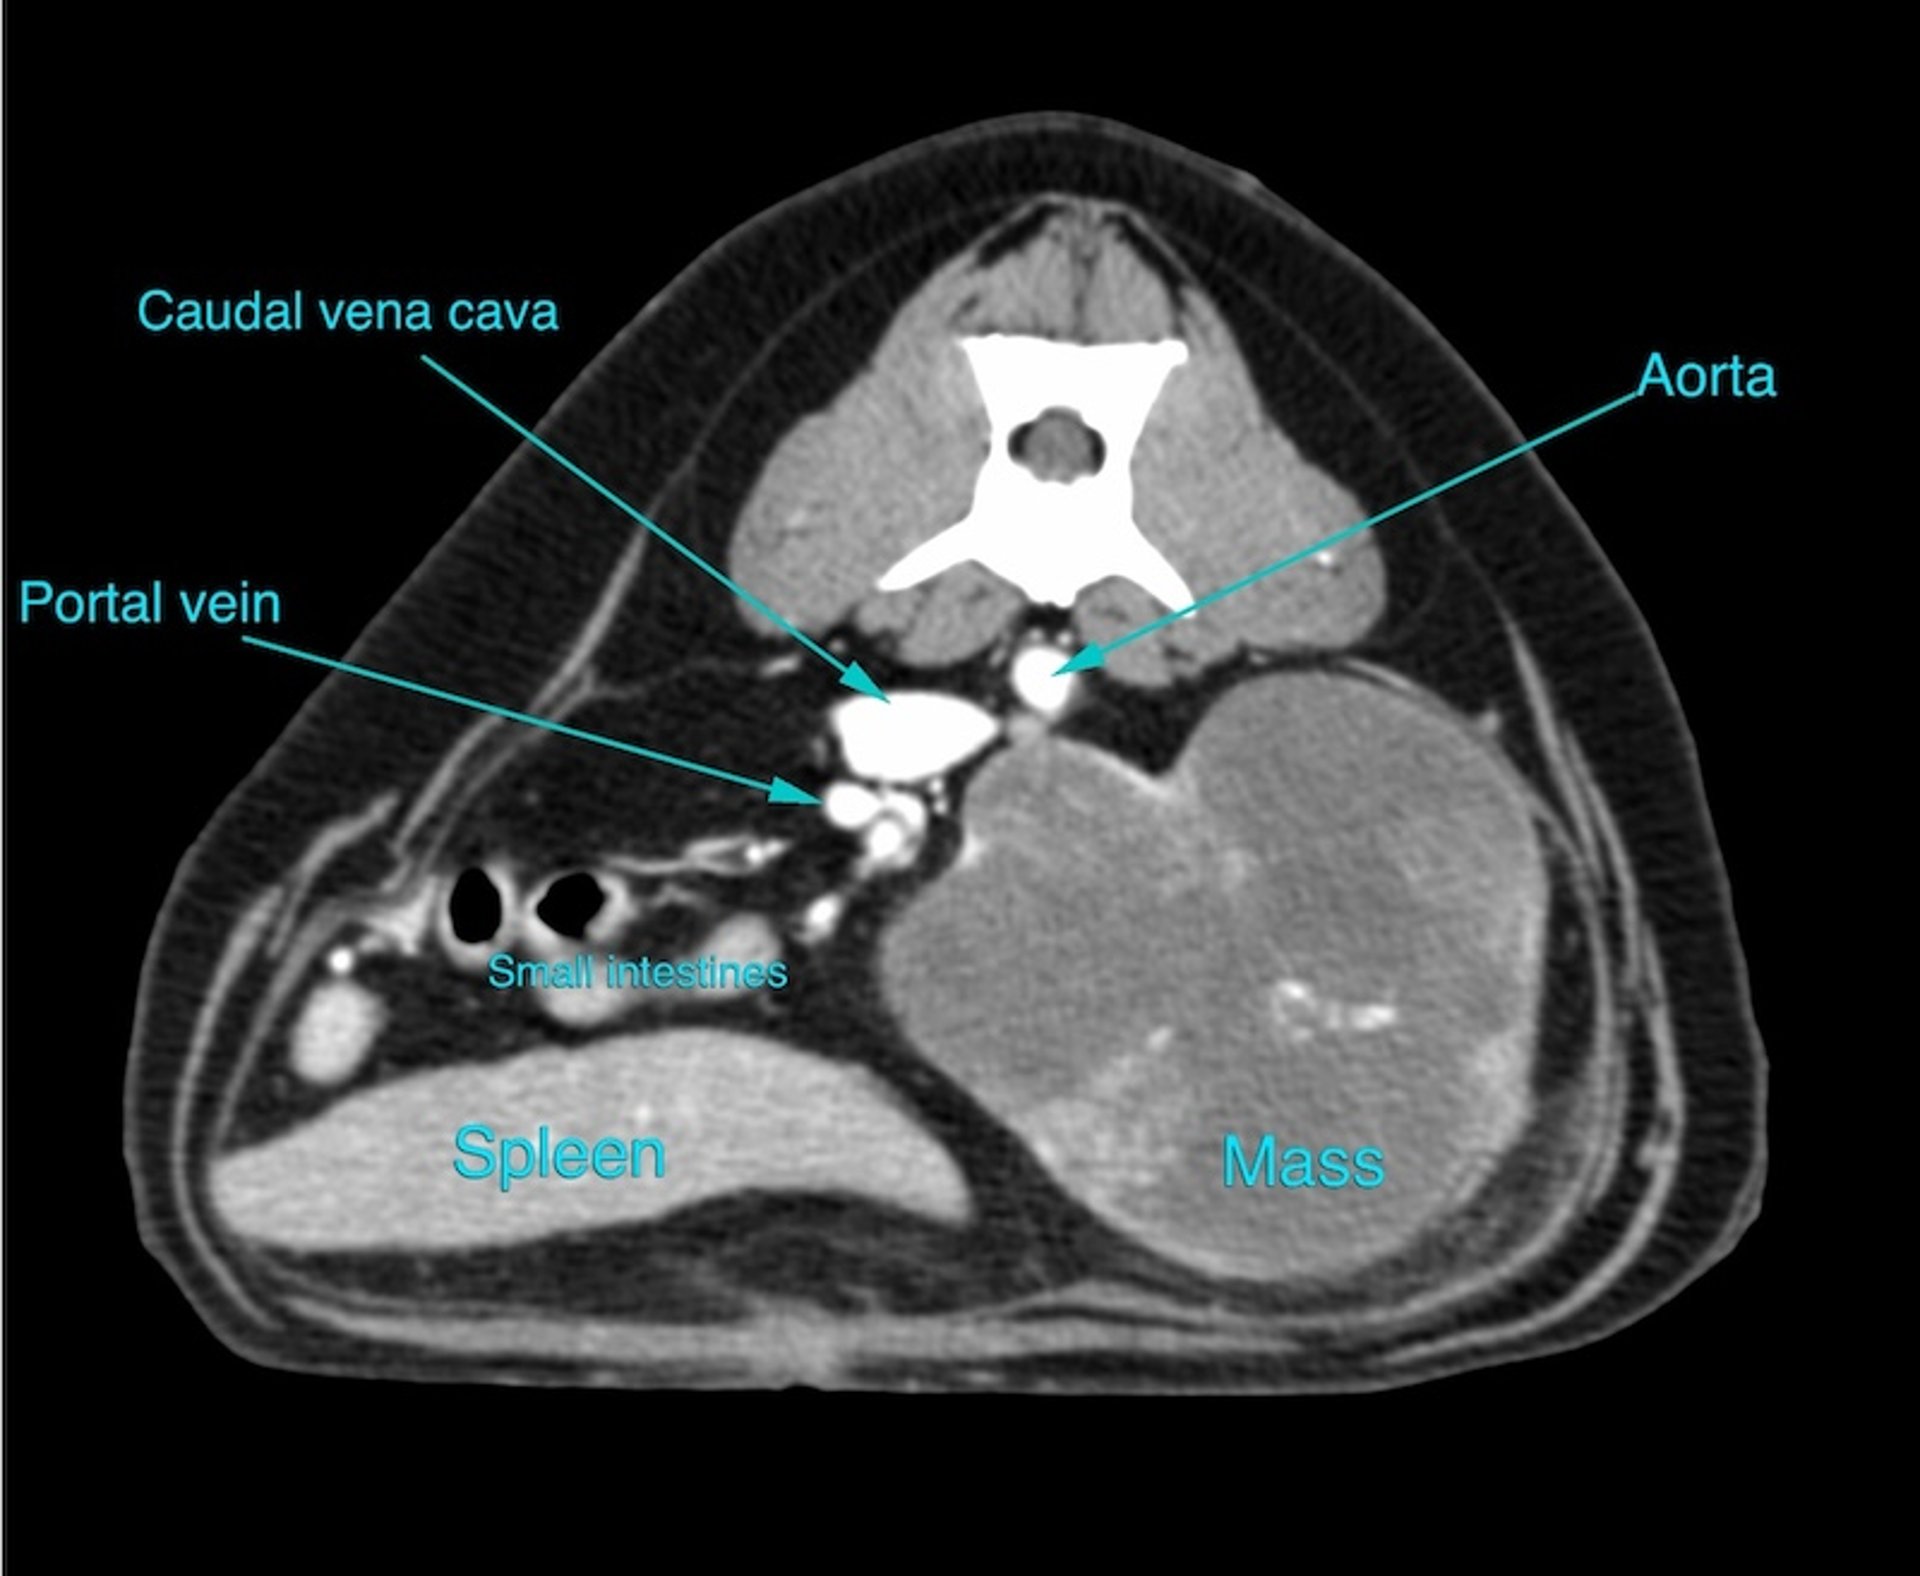

El lado izquierdo del paciente está a la derecha de la imagen. Imagen de TC transversal del abdomen medio de un perro mostrada en una ventana de tejido blando, después de la administración de contraste intravenoso, para una evaluación adicional de una masa abdominal. Finalmente se determinó que la masa provenía del riñón izquierdo; esto se sospechó en las radiografías, pero la TC permite una caracterización más detallada y ayudó con la planificación quirúrgica. El diagnóstico final fue un carcinoma renal.

Cortesía del Dr. Timothy Manzi.